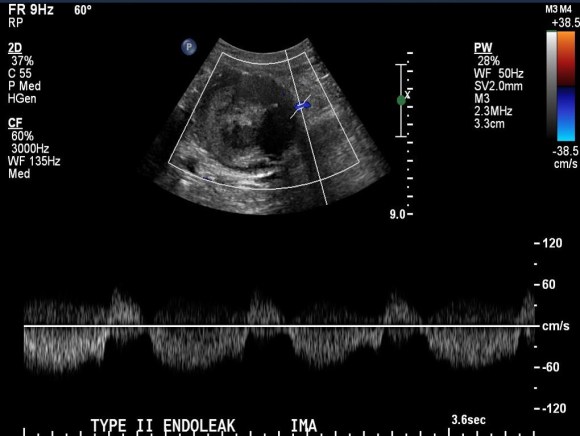

The patient had a successful EVAR or an eccentric infrarenal AAA which in followup grew due to the presence of a type II endoleak from the inferior mesenteric artery. This was seen on the CTA and duplex ultrasound. Planning for assessment and treatment involved analyzing the CTA in centerline, tracking the source of the arterial blood flow into the sac.

The embolization with NBCA sealed the IMA and the cavity in the AAA sac. This was checked with intraoperative duplex, done with a transabdominal aortic probe.

Transabdominal aortic duplex is easier on sleeping patient and potentially gives more information than arteriography alone. The patient in followup had no endoleak and demonstrated sac shrinkage.